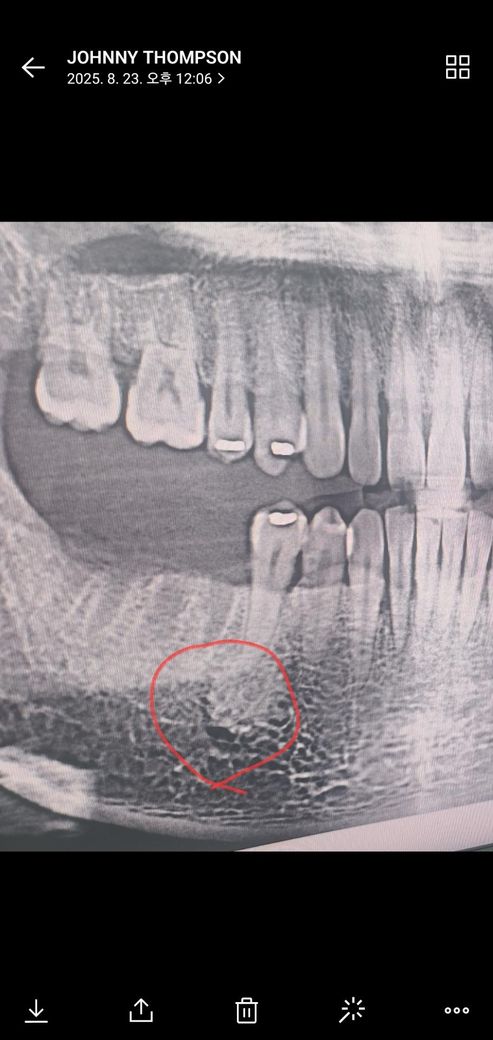

치과에서 엑스레이 사진을 찍었는데 턱뼈에 동그란게 찍혔어요

치아 상태 확인 차원에 처음 x-ray를 찍고 발치 후 한달 지나 임플란트 진행을 하기 위해 뼈 상태 알아보기 위한 x-ray를 다시 촬영했는데 처음엔 몰랐는데 이전 x-ray 사진에도 동그랗게 뭔가 있는게 나왔어요 의사쌤도 별거 아닌거 같지만 혹시 모르니 대학병원 가서 검사를 해보는게 좋다고 하셔서 문의 드려봅니다.

사진상에서 하얗게 보이는 것은 단순 골 치밀화로 보이지만 혹시 모르니 가보셔도 될 것 같습니다.

사진에 보이는건 크게 문제가되는건 아니지만 제 생각에는 이공이라는 턱아래 신경이 나오는 구멍이 보이는거 같습니다.

사진으로만 봤을 경우에는 치조골이 국소적으로 치밀화 되어 있는것으로 보입니다.

대부분 문제를 발생시키지는 않기 때문에 너무 걱정하지 않으셔도 되지만 해당부위가 불편하거나 걱정이 된다면 대학병원치과에서 진료를 받아 보는것이 좋습니다.

1. 검은 둥그런 점은 이공(신경이 지나가는 길) 같습니다

2. 그 외 흰색 부분부분 진한건 정상 골반응 같습니다